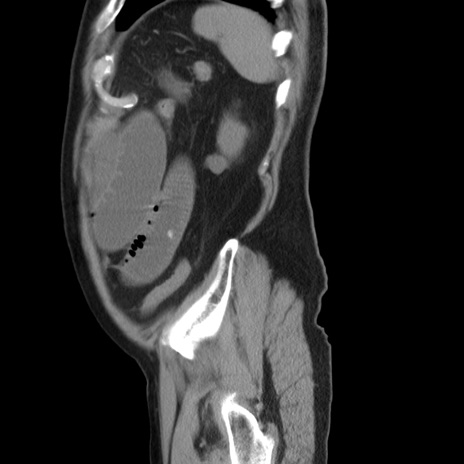

症例20(矢状断像)

【症例】 60歳代男性

【主訴】 腹部膨満、嘔吐

【現病歴】5日前頃より倦怠感を認め食事量減少し4日前の朝嘔吐、食事摂取困難となった。 3日前近医受診し点滴施行され整腸剤などを処方された。 当日他院を受診し、腹部膨満著明、炎症反応の上昇(CRP10.8、WBC11200)あり、紹介受診となる。

【身体所見】 意識JCS1 受け答えがはっきりしないBP 111/57mHg、 P 67bpm、、BT35.2°C、SpO2 97%(RA)、 腹部:膨隆、打診で鼓音あり、全体的に圧痛有り、腸蠕動音(-)、反跳痛ははっきりせず。

【データ】WBC 11400、CRP 14.20